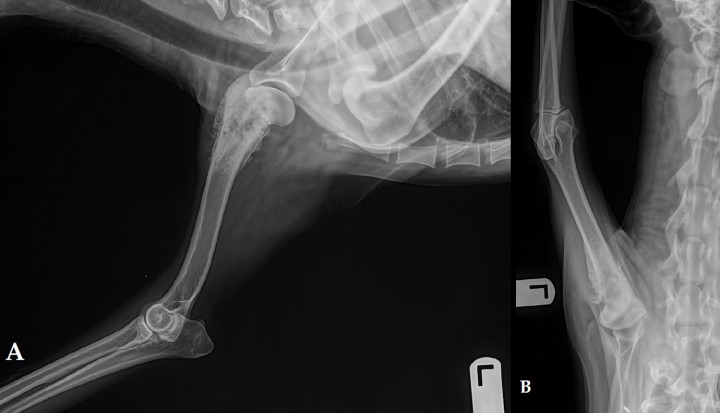

Fracturas complejas

Solución ideal para fracturas con múltiples fragmentos o alta inestabilidad.